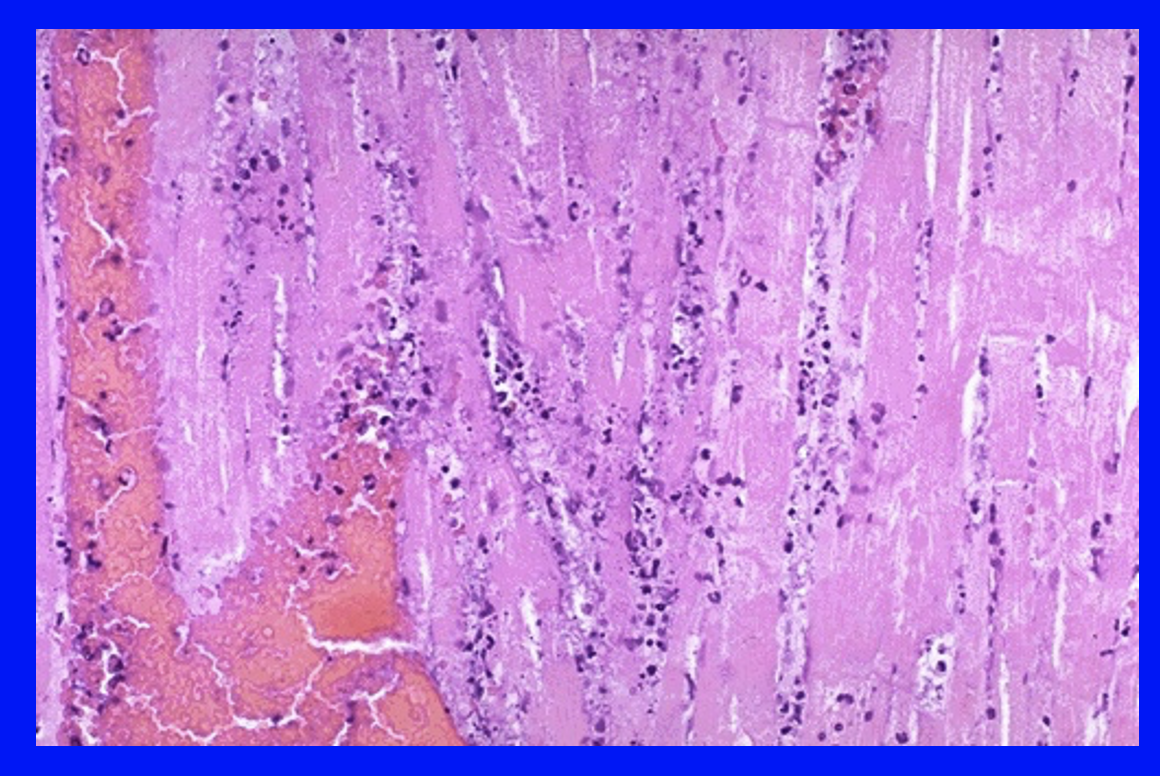

What histological changes are seen 6-24h after an MI?

A

loss of nuclei, homogenous cytoplasm necrotic cell death

Q

What histoloigical changes are seen 1-3 days post-MI?

Infiltration of polymorphs then macrophages (clear up debris)